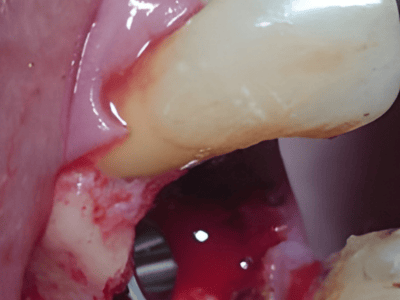

Dr. Deeksha Bhardwaj is a highly skilled dental specialist in Greater Noida, specializing in

Periodontics, Dental Implants, and Advanced Gum Care. With a BDS and MDS in Periodontics, she

provides expert treatment for gum diseases, receding gums, and dental implant procedures using the

latest technology.

Dr. Bhardwaj holds a BDS and MDS in Periodontics, specializing in gum health, dental implants, and advanced periodontal care.

Dr. Bhardwaj specializes in Periodontics, offering treatments for gum diseases, dental implants, laser dentistry, root canal treatments (RCT), teeth whitening, smile makeovers, and general dental care.